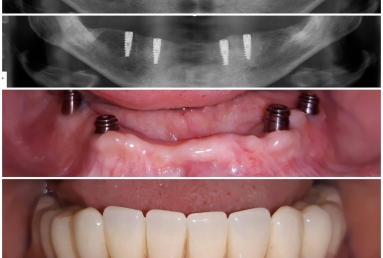

Mobile Prosthesis fixed with 4 locators on 4 Alpha BIO Nobel dental implants

Mobile Prosthesis fixed with 4 locators on 4 Alpha BIO Nobel dental implants.

Female patient with advanced periodontal disease has mobility of all teeth and old dental work. All mandibular teeth were extracted and replaced with 4 dental implants ( Alpha bio Nobel).

The mobile prosthesis is fixed with 4 locators that firmly stabilise it. The mastication, talking and aesthetics is very comfortably and safely obtained.